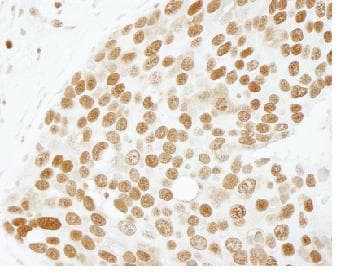

Rabbit Polyclonal PC4 antibody. Suitable for IHC-P and reacts with Mouse, Human samples. Cited in 4 publications. Immunogen corresponding to Synthetic Peptide within Human SUB1.

Applications IHC-P

Species Reactivity Human, Mouse